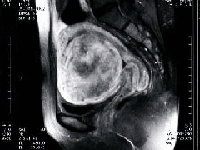

塞栓術前

黒く抜けているのは全て壊死におちいった筋腫